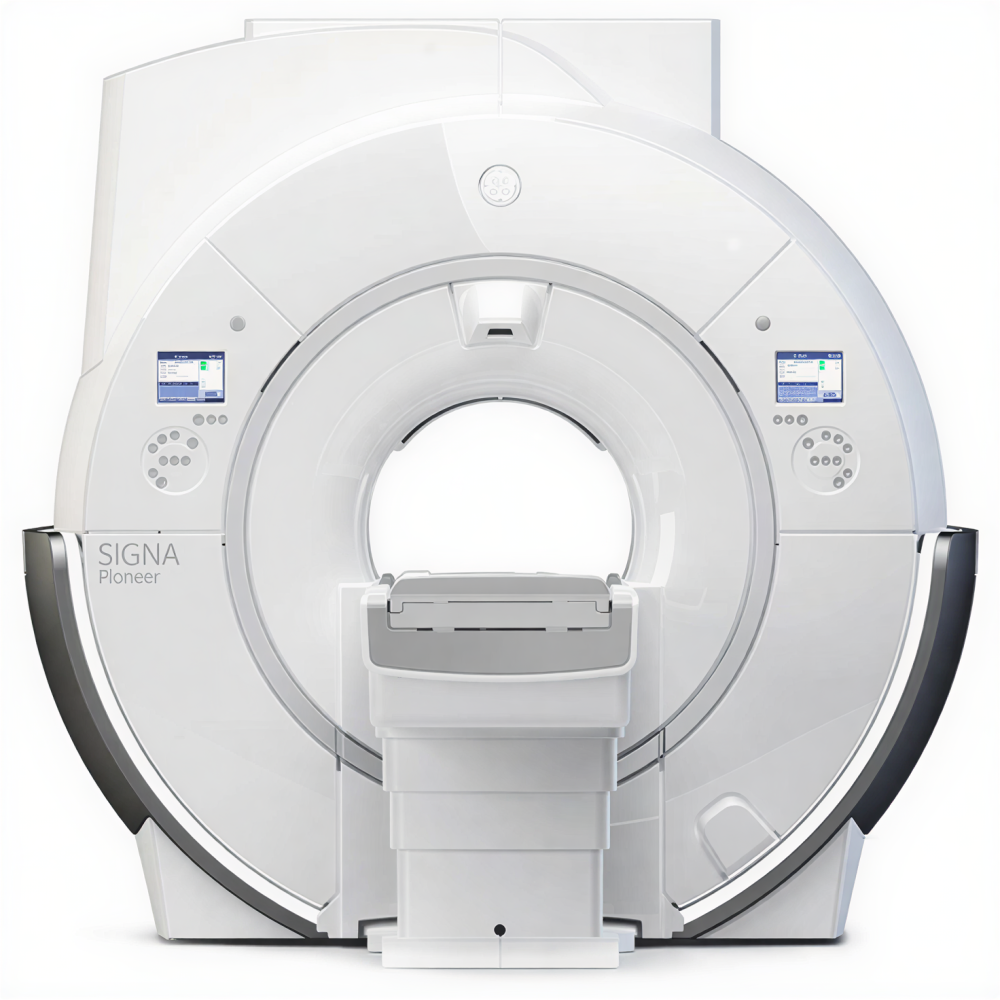

Магнитно-резонансный томограф GE SIGNA Pioneer 3 Тл — премиальная система для продвинутой МР-диагностики

GE SIGNA Pioneer относится к актуальному поколению 3T-систем семейства SIGNA, в которых сделан акцент на сочетании высокой однородности поля, развитой градиентной системы и цифровой архитектуры приёма сигнала. Платформа проектировалась как универсальное решение для нейрорадиологии, онкологии, кардиологии, ортопедии и целотельных исследований. Широкий тоннель и комфортный стол обеспечивают удобство позиционирования пациента и снижают долю прерванных исследований, а развитые средства коррекции движения и шумопонижения (включая технологии Silent и современные алгоритмы реконструкции) помогают получать стабильные диагностические изображения даже у сложных категорий пациентов.

- Премиальная 3T-платформа семейства SIGNA для клинической и исследовательской МР-диагностики головного мозга, позвоночника, суставов, органов и всего тела.

- Широкий тоннель и эргономичный стол пациента для повышения комфорта, снижения клаустрофобии и уверенной работы с пациентами высокой массы тела.

| Тип / класс системы | Высокопольный магнитно-резонансный томограф закрытого типа для обследования всего тела |

| Напряжённость магнитного поля | 3,0 Тл |

| Тип магнита | Сверхпроводящий магнит с широким тоннелем |

| Диаметр тоннеля для пациента | 70 см |